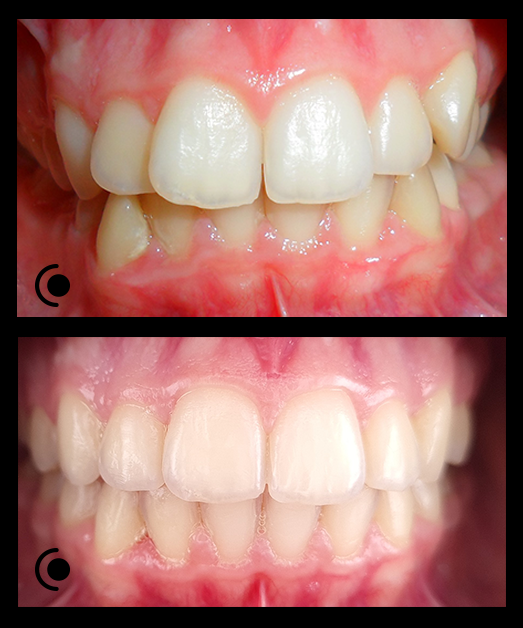

O našoj kvaliteti najbolje govore naši rezultati!